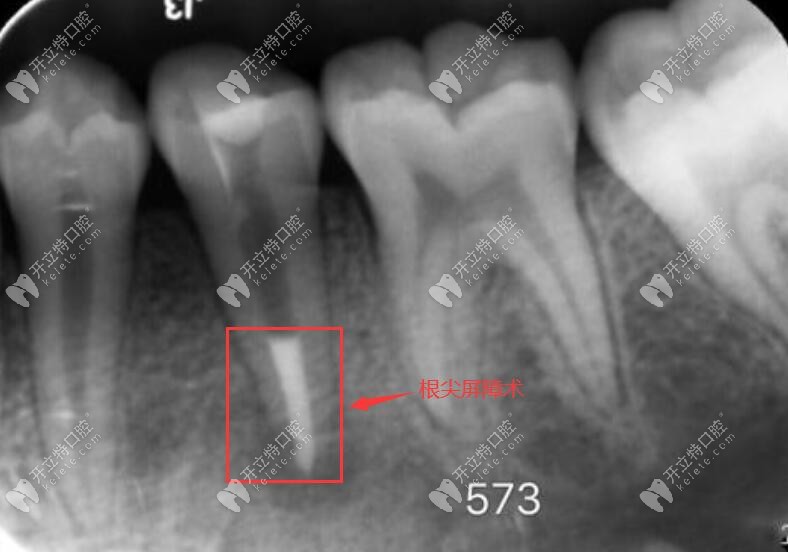

這兩者主要用于根尖屏障術(shù)和蓋髓術(shù),也就說在顧客的有根尖炎癥、根尖孔未閉合、牙髓壞死、伴有跟根尖周炎、根尖未發(fā)育完全的狀態(tài)下的一個修補,都可以使用的根尖屏障術(shù)進行治療。

如圖,根尖屏障術(shù):通俗的講就是把已經(jīng)有炎癥的牙髓去掉,并使用mta或者iroot材料,把根尖位置堵住,將牙周膜和牙髓隔離開。